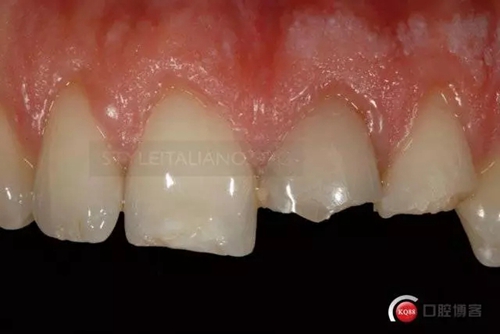

Control one month check shows a natural smile

344244.jpg

And the vestibular

333621.jpg

and palatal tissue healing